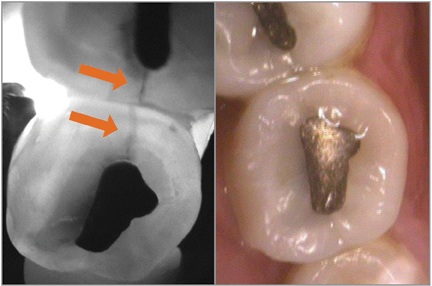

By using CariVuTM, cracks are easily visible to both clinicians and patients.

There are a lot of different things that it does that are unique and useful, but the No. 1 thing I like it for is fractured teeth. I used to call a fractured tooth the mystery tooth. I would say, ‘If a tooth is acting funny in a bunch of different ways, that leads to me to think fracture.’ But I felt like it wasn’t certain and I don’t like that. I like to show a person the crack. Unless it’s an incredibly large fracture, you can’t see fractures on an X-ray at least 99.9 percent of the time. I wear loupes, too, so sometimes I can see them. An intraoral camera sometimes can pick them up. Sometimes there are superficial cracks everywhere. With CariVu, when you suspect the tooth has fractures, you put it on and take an image. I can put that image up on the screen, and the patient can see it just as easily as I can. And the insurance companies can see those cracks as well. I love CariVu for that.

That’s true. Insurance gets kicked back with, ‘Why are you putting a crown with an occlusal amalgam?’ I send them the CariVu image and say, ‘Because there’s a huge fracture going through it, and the patient is going to break this tooth.’ The insurance company can see it, and everyone agrees. You can’t argue with facts.

From the patients’ standpoint, they don’t get that much out of the X-ray. They get some information out of the intraoral camera, but then they really see with the CariVu. From the doctor’s side of things, if there was overlap on the bitewing, which happens all the time with crowded teeth, you can miss the decay. But it shows up on CariVu images even more than on an X-ray. There’s no guesswork with the CariVu looking for interproximal decay. It’s dark; it shows up. For a dentist’s eye, there’s no question now.